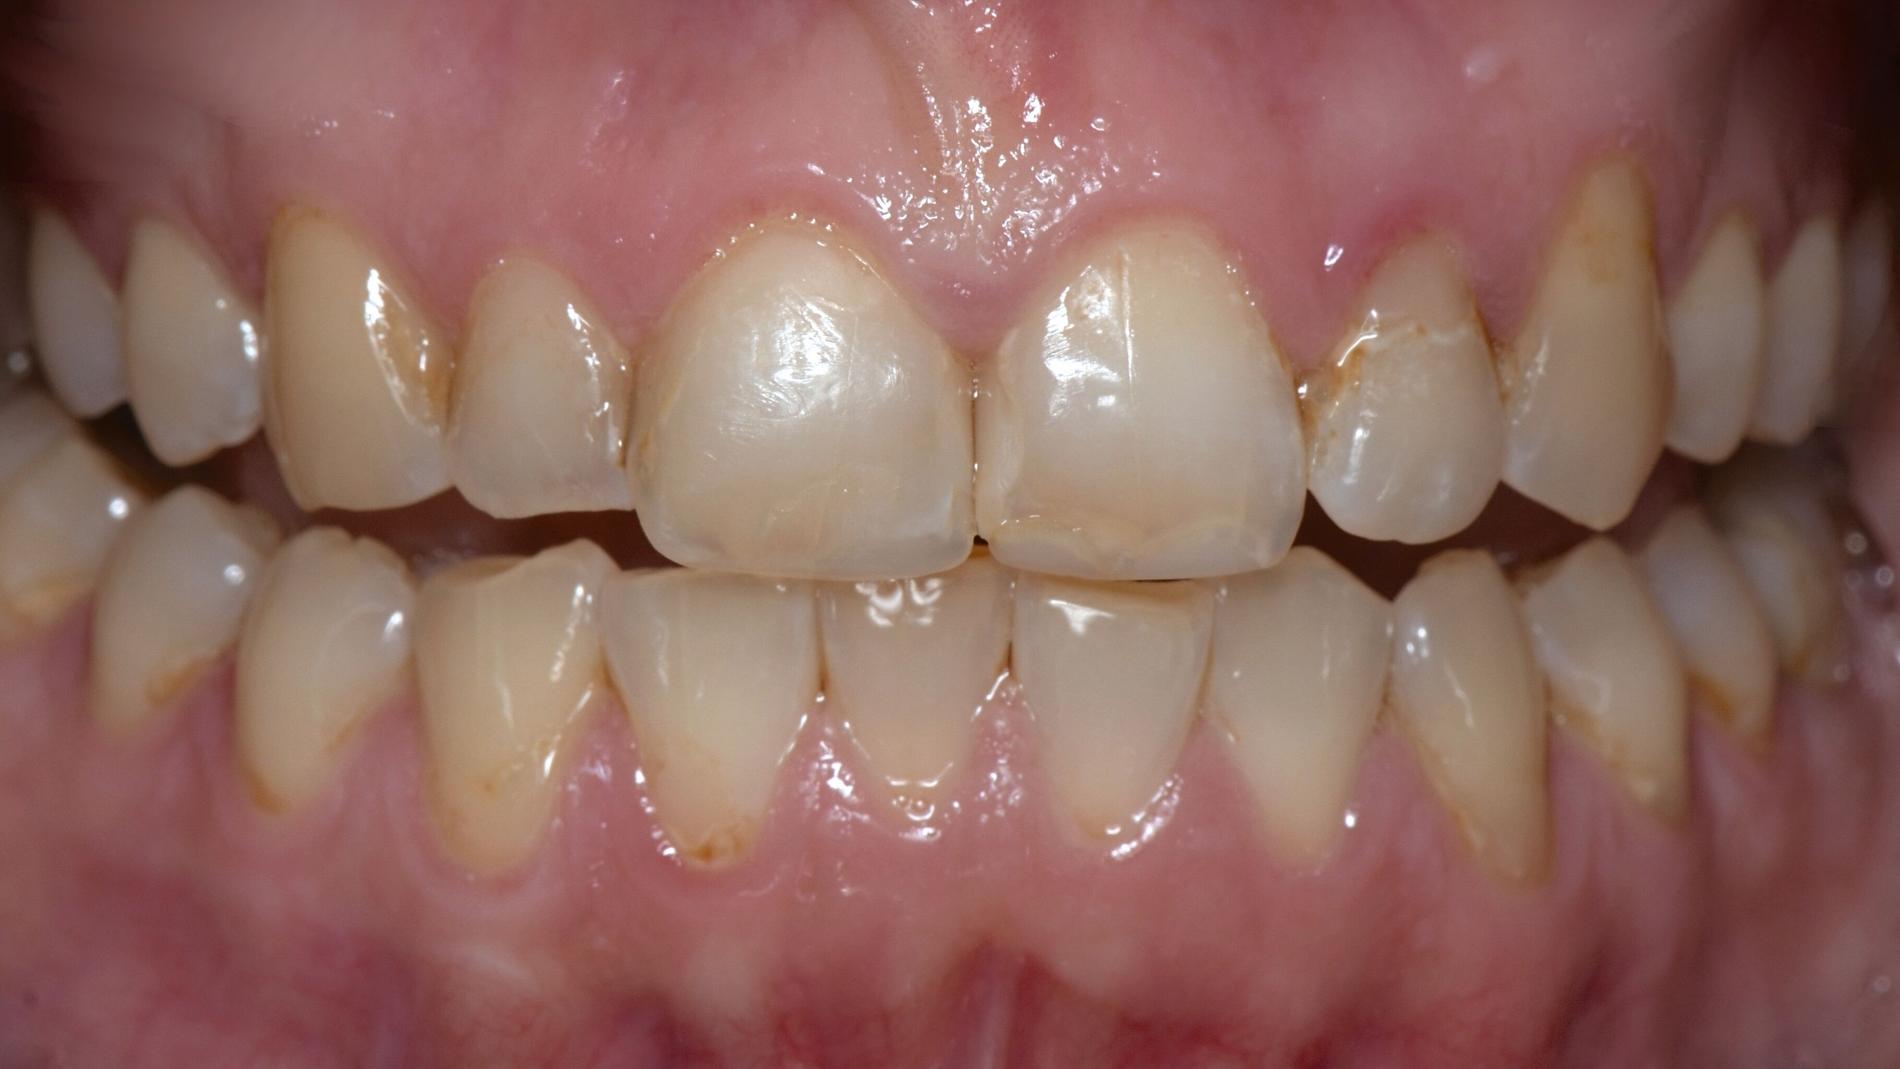

In der extraoralen Untersuchung zeigte sich ein trockenes Hautbild ohne weitere Auffälligkeiten. Intraoral waren multiple initiale Läsionen, eine erhöhte Plaqueakkumulation, sowie diverse Kompositrestaurationen im Seitenzahnbereich auffällig (Abbildungen 2a und 2b).

Attritionen im Front- und im Seitenzahnbereich

Die Achse-II-Diagnostik zeigte im Screening mit dem Fragebogen „Depression, Anxiety and Stress Scale“ (DASS) positive Befunde in den Dimensionen Depression, Angst und Stress. Es folgte die Durchführung einer aktuellen OPG-radiologischen Diagnostik. Diese zeigte Opazitäten im Sinne von Füllungen an diversen Zähnen und einer Wurzelfüllung 36; weiterhin eine deutlich abgeflachte und dysmorphe Struktur des Condylus articularis rechts sowie eine Abflachung des Condylus articularis links (Abbildung 3).